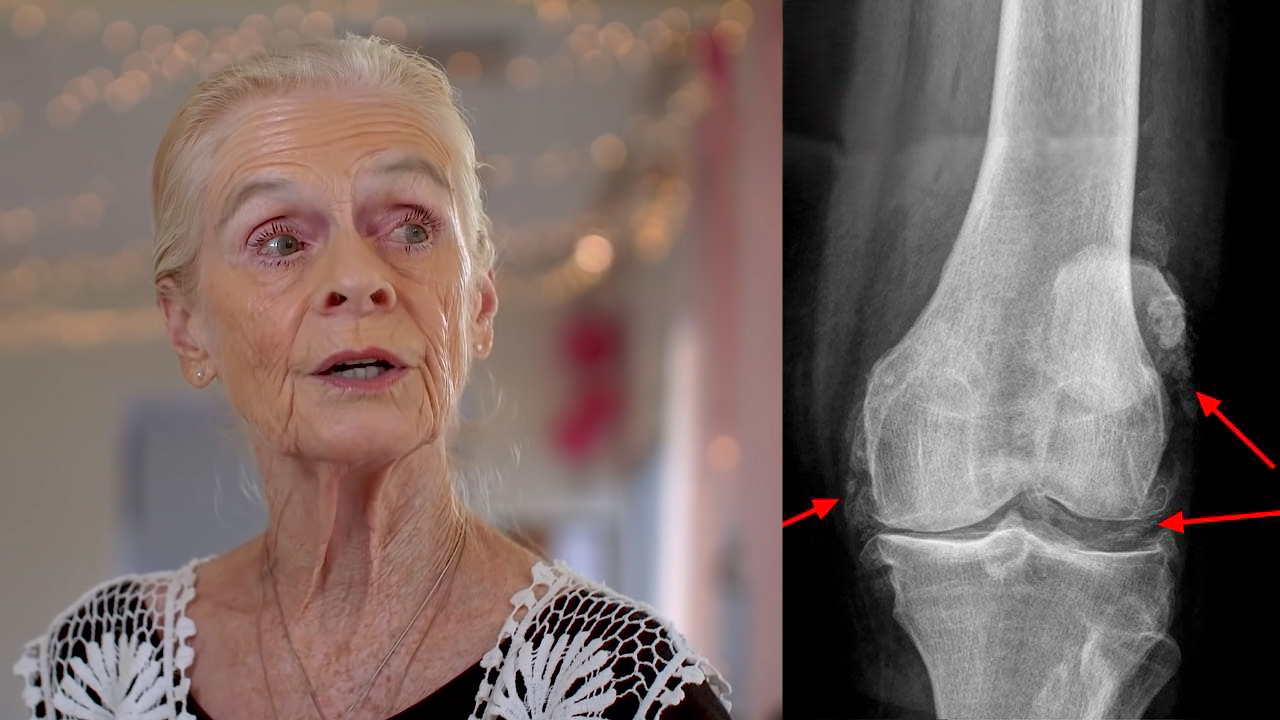

Погляньте на ці знімки, ви бачите, що на правому знімку суглобова щілина відсутня, кістки труться один об одного, викликаючи сильний біль. І цей процес дуже важко зупинити! Через пару років людина стане інвалідом і не зможе себе обслуговувати.